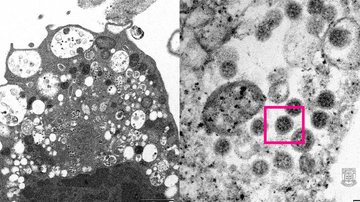

Coronavírus